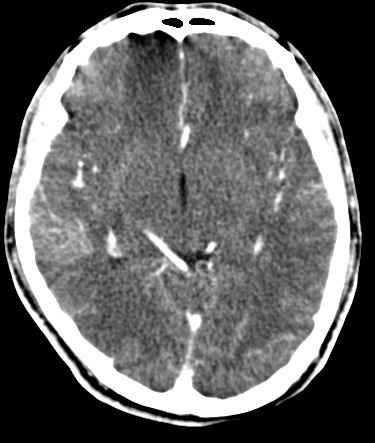

男,31岁,头疼就诊,其他不祥。

考虑右颞叶脑血管畸形伴出血。avm可能大,建议dsa。

平扫见右颞叶、右侧脑室后角旁略高密度影,增强未见明显病灶,基本正常。不放心做mri检查

病灶呈略高密度,周围伴环形水肿,无强化/无异常av影........

考虑为:1.脑内小血肿?   2.脑灰质异位?   建议mri检查........

考虑右颞叶脑血管畸形伴出血。考虑静脉血管瘤,深部型的,avm不除外,建议dsa。